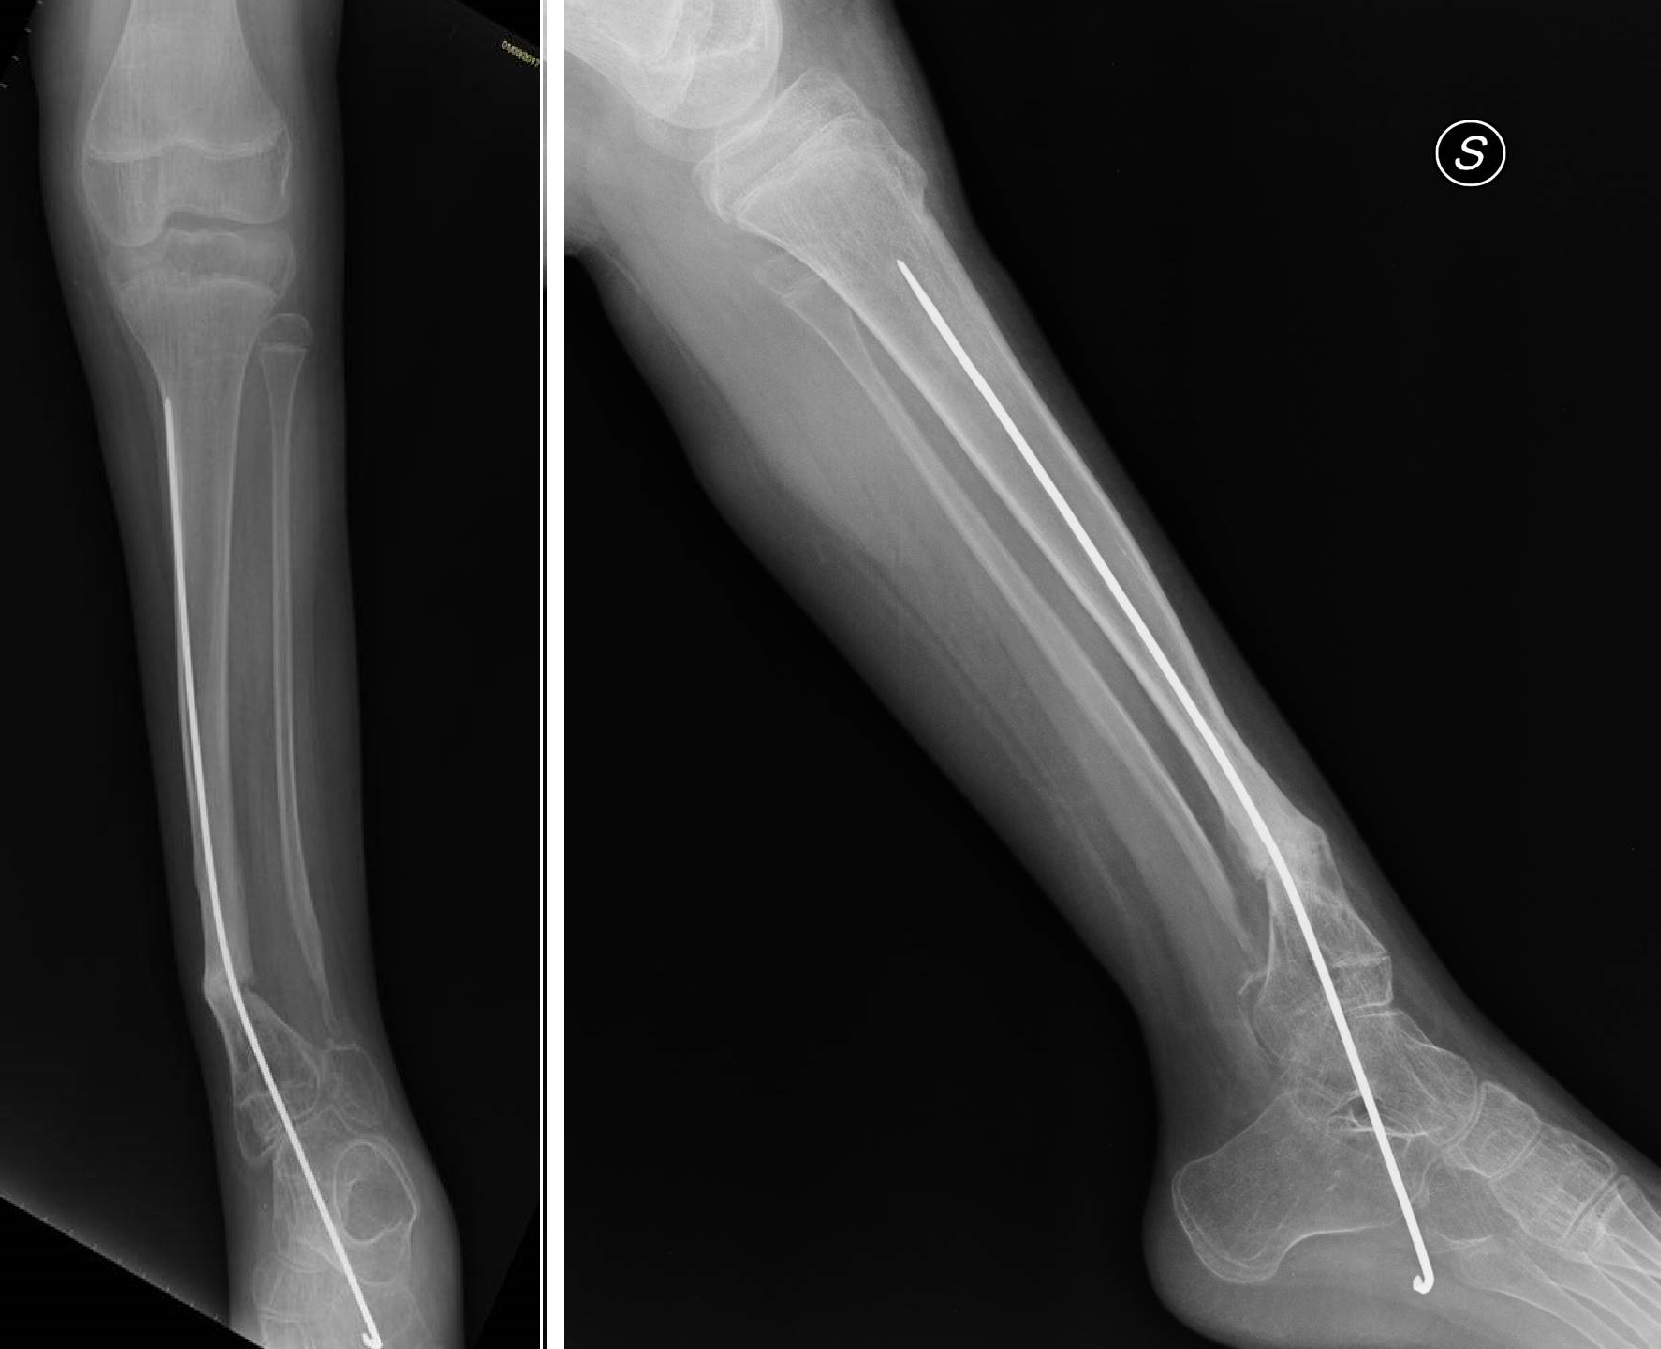

1) L'inchiodamento endomidollare (chiodi di Rush o Kirschner o telescopici) dopo accurata pulizia chirurgica dei monconi di pseudoartrosi e del periostio limitrofo, viene aperto il canale midolalre mediante perforatori per garantire adeguato apporto ematico sui monconi quindi si ottiene la stabilizzazione della lesione con un infibulo endomidollare di lunghezza e calibro adeguato alle dimensioni della tibia per favorire la consolidazione si aggiungono adiuvanti biologici come innesti ossei prelevati dalla stessa cresta iliaca del paziente e/o concentrato di mesenchimali prelevato dalla cresta iliaca (MSC); nel caso dei chiodi di Rush o Kirschner l'infibulo è inserito dal basso attraverso il calcagno, attraversa l'articolazione tibio-tarsica per dare sufficiente stabilità, e consente di posizionare il piede in leggera supinazione per prevenire la deformità in valgo pronazione tipica della patologia. Tali chiodi richiedono la sostituzione periodica ( 2-3 anni) per crescita del paziente.